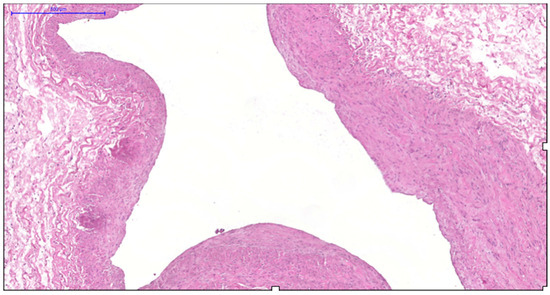

Age- and Varicose Disease-Associated Changes in the Muscular Components of the Great Saphenous Vein

by Khurshed A. Abduvosidov, Irina A. Chekmareva, Valeria G. Shestakova, Irina N. Shabanova, Alexander G. Alekseev, Edgar S. Kafarov, Alexander A. Palalov, Irina N. Yashina and Evgeny N. Galeysya

J. Clin. Med. 2025, 14(18), 6448; https://doi.org/10.3390/jcm14186448 - 12 Sep 2025

Varicose disease and other age-related vascular illnesses are extremely prevalent among the adult population. Despite this, research devoted to involutive changes in the veins of the lower extremities is rare and fragmented. Complex morphological evaluation of the wall of the vein related to [...] Read more.

Varicose disease and other age-related vascular illnesses are extremely prevalent among the adult population. Despite this, research devoted to involutive changes in the veins of the lower extremities is rare and fragmented. Complex morphological evaluation of the wall of the vein related to age and varicose disease can add valuable data to fundamental geriatric and vascular medicine. Objectives: The study was designed to determine the age-related changes in the muscular component of the great saphenous vein and changes associated with varicose disease. Materials and Methods: A morphological study of a specimen of the great saphenous vein was conducted on 55 deceased individuals and 80 patients with varicose disease. Four age subgroups were identified: young, middle-aged, elderly, and senile. A total of 135 fragments of the great saphenous vein were evaluated. Histological, morphometric, and electron microscopic studies were performed. A quantitative analysis of the volumetric fraction of muscular components was calculated using the Shapiro–Wilk test, Kruskal–Wallis (ANOVA) and Mann–Whitney methods with Bonferroni correction. Results: Our study showed that the amount of connective tissue elements between bundles of smooth muscle cells increased with age. In patients with varicose disease, we observed an appearance of connective tissue fibers among smooth muscle cells, more pronounced with the disease progression. The structure of smooth muscle cell changes. Thus, we observed hypertrophy and phenotypic heterogeneity of cells with subsequent destruction of communicative contacts. The values of subintimal longitudinally arranged smooth muscle cells reached their maximum in middle age in both normal and varicose veins, while significant decrease occurred in elderly and senile patients. Quantitative indicators of circularly arranged smooth muscle cells of the middle layer did not change with age but significantly decreased in varicose disease. Age-related changes are characterized by an increase in the proportion of smooth muscle cells in the outer layer. In varicose veins, in young and middle-aged patients, the content of bundles of longitudinally arranged smooth muscle cells in the outer layer was higher compared to the age norm, with a significant decrease in senile age. Conclusions: The age norm of the muscular component of the great saphenous vein wall is characterized by an increase in the volumetric fraction of subintimal longitudinally arranged smooth muscle cells in middle age, the volumetric fraction of circularly arranged smooth muscle cells of the middle layer remains unchanged, and the volumetric fraction of bundles of longitudinally arranged myocytes of the outer layer increases. With age in varicose disease, sclerotic changes progress in the structure of the great saphenous vein at the tissue, cellular, and intracellular levels, leading to a decrease in the volumetric fraction of all muscular components of the great saphenous vein structure. Full article

Show Figures

Figure 1